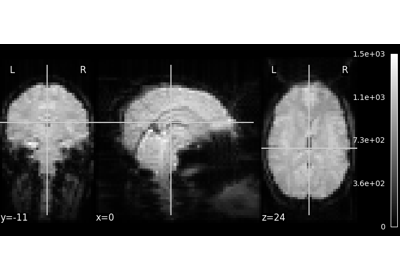

Exercise: Varying the amount of smoothing in an image

Compute the mean EPI for one individual of the brain development dataset downloaded with nilearn.datasets.fetch_development_fmri and smooth it with an FWHM varying from 0mm to 20mm in increments of 5mm

Intermediate steps:

1. Run nilearn.datasets.fetch_development_fmri and inspect the .keys() of the returned object

2. Check the nilearn.image module in the documentation to find a function to compute the mean of a 4D image

3. Check the nilearn.image module again to find a function which smoothes images

4. Plot the computed image for each smoothing value

A solution can be found here.